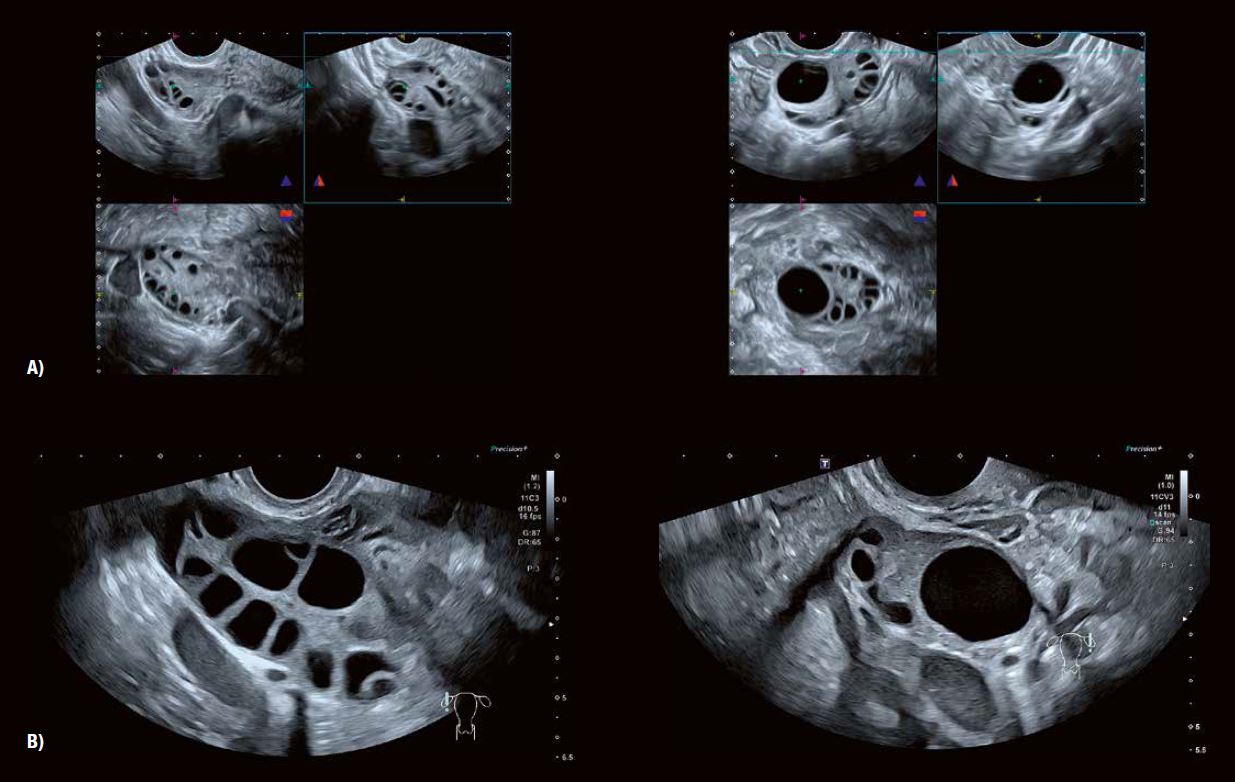

Рис. 3 A: 3D анатомічні площини показують типову мультифолікулярну природу структури фолікулів яєчників у віковій групі від раннього до середнього та пізнього підліткового віку.

Рис. 3 B демонструє зміну характеристик фолікулів та строми у жінок, наприклад, у віці від 25 до 39 років, особливо після пологів.

Рис. 3 C: Типовий вигляд у віковій групі 40 років.

Рис. 3 D: 2D- та 3D-зображення (Luminance) показують фолікули жінок у віці від 45 до 50 років. На відтвореному зображенні чітко видно контури фолікулів, що складаються з гранульозних та текальних клітинних шарів.

Ультразвукові властивості яєчників значно варіюються відповідно до морфологічних змін, що відбуваються залежно від віку та кількості пологів. Анатомічні висновки, отримані в результаті масштабного спостережного дослідження, проілюстровані на рисунку 2.

10 000 пацієнток у віці від 15 до 60 років  були обстежені за допомогою 3D (об'ємної) трансвагінальної ультразвукової діагностики.

Результати стосуються ультразвукових ознак, що спостерігаються в середині проліферативної фази менструального циклу.

Яєчники мають характерну «багатофолікулярну» структуру після настання статевої зрілості і, як правило, залишаються такими до настання вагітності або до настання середнього віку у жінки. Спостерігається тенденція до збільшення розміру фолікулів з відповідним зменшенням їх кількості на цій стадії овуляційного циклу, яка триває протягом усього репродуктивного періоду життя.

Ця зміна у структурі фолікулів супроводжується одночасним розвитком строми яєчників. Зміни, зображені на рис. 2, добре відповідають коливанням рівнів ФСГ та АМГ у сироватці крові, особливо у старших вікових групах.

Рис. 2: Зміни в структурі фолікулів яєчників та строми з віком та кількістю пологів. Висновки великого дослідження з використанням 3D (об'ємного) трансвагінального ультразвукового дослідження.